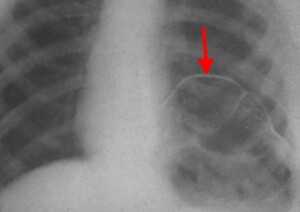

Основное место в диагностике повреждений диафрагмы принадлежит лучевым методам диагностики (7-9): рентгенологическому исследованию, компьютерной томографии. Разрыв диафрагмы установлен у 6 пострадавших при рентгенологическом исследовании (рис 1, 2), у 1 больного с тяжелой сочетанной травмой — при компьютерной томографии, у 3 больных — как интраоперационная находка. Закрытая травма порой не приводит к возникновению симптомов, которые являются патогномоничными для повреждений диафрагмы. При небольших повреждениях диафрагмы клиника, как правило, бывает скудной и стушевывается другими более тяжелыми травмами сочетанных повреждений и является находкой при рентгенологических исследованиях.

М., 20 л. Сочетанная травма. Закрытый перелом костей таза, разрыв уретры, Разрыв правого купола диафрагмы. Тяжесть повреждений по шкале оценки ВПХ П. (МТ) — 13 баллов, ВПХ (СП) — 29 (Гуманенко Е.К. 1999 г).

Больной М., 23 г. Рентгенологическая картина (прямая и боковая проекции) повреждения правого купола диафрагмы. Присасывание в плевральную полость ткани правой доли печени. Проведена лапаротомия, эпицистостомия, ушивание разрыва диафрагмы. Пациент выписан в удовлетворительном состоянии. Восстановление разрыва уретры проведено вторым этапом в урологической клинике